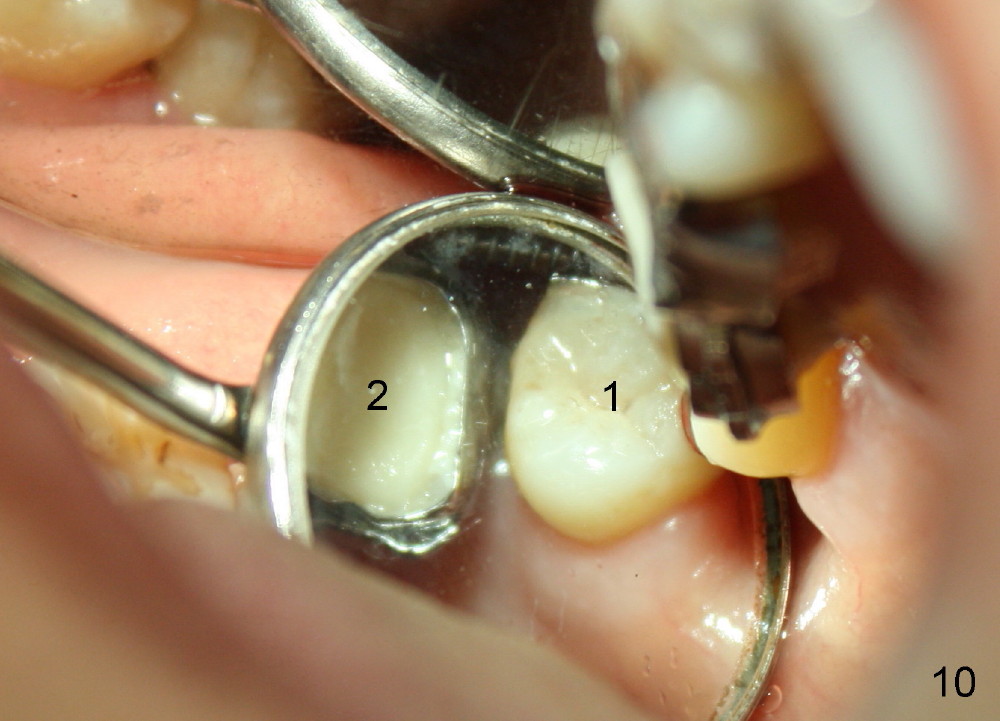

A 48-year-old lady is a dental phobic and has generalized chronic periodontitis. Bone loss around the tooth #2 has been severe for the last 5 years (Fig.1,2 *). Finally she agrees to have #2 (symptomatic) extracted and immediate implant placed (Fig.3 I). A 7x17 mm implant has to be used to achieve primary stability. The remaining buccal and lingual gaps are filled with allograft and membrane (Fig.4 *). Fig.5 shows that there is a space between the tooth #1 (asymptomatic) and the immediate implant (I). The wound/socket is protected by applying perio dressing around an abutment (Fig.6 A). Postop the patient is pain free; the perio dressing dislodges by itself. She returns 3.5 months later for restoration; but the tooth #1 has shifted mesially (Fig.6 arrow). The patient is not so willing to have #1 removed. Bands and bracket are placed in the neighboring teeth including a provisional crown to move the shifted tooth (with mobility) distally (Fig.7,9). The 2nd reason for #1 shifting is abnormal occlsual scheme on the right posterior region (Fig.8); mobility of #1 is the 1st one. The 3rd one is probably bruxism. In 5-6 weeks, the tooth #1 has moved to a desirable position (Fig.10, as compared to Fig.3,5). There is enough space for restoration (Fig.11,12).